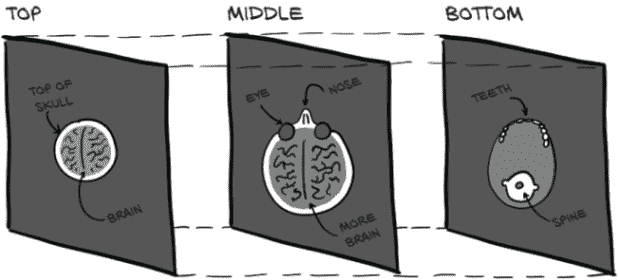

如果您的项目需要区分近处猫和远处猫,或者左边的猫和右边的猫,那么分割可能是正确的方法。迄今为止我们实现的图像消费分类模型可以被看作是漏斗或放大镜,将大量像素聚焦到一个“点”(或者更准确地说,一组类别预测)中,如图 13.4 所示。分类模型提供的答案形式为“是的,这一大堆像素中有一只猫”,或者“不,这里没有猫”。当您不关心猫在哪里,只关心图像中是否有猫时,这是很好的。

图 13.4 用于分类的放大镜模型结构

重复的卷积和下采样层意味着模型从消耗原始像素开始,产生特定的、详细的检测器,用于识别纹理和颜色等内容,然后构建出更高级的概念特征检测器,用于眼睛、耳朵、嘴巴和鼻子等部位³,最终得出“猫”与“狗”的结论。由于每个下采样层后卷积的接受域不断增加,这些更高级的检测器可以利用来自输入图像越来越大区域的信息。

不幸的是,由于分割需要产生类似图像的输出,最终得到一个类似于单一分类列表的二进制标志是行不通的。正如我们从第 11.4 节回忆的那样,下采样是增加卷积层接受域的关键,也是帮助将构成图像的像素数组减少到单一类别列表的关键。请注意图 13.5,它重复了图 11.6。

图 13.5 LunaModel块的卷积架构,由两个 3×3 卷积和一个最大池组成。最终像素具有 6×6 的接受域。

在图中,我们的输入从左到右在顶部行中流动,并在底部行中继续。为了计算出影响右下角单个像素的接受域–我们可以向后推导。最大池操作有 2×2 的输入,产生每个最终输出像素。底部行中的 3×3 卷积在每个方向(包括对角线)查看一个相邻像素,因此导致 2×2 输出的卷积的总接受域为 4×4(带有右侧的“x”字符)。顶部行中的 3×3 卷积然后在每个方向添加一个额外的像素上下文,因此右下角单个输出像素的接受域是顶部左侧输入的 6×6 区域。通过来自最大池的下采样,下一个卷积块的接受域将具有双倍宽度,每次额外的下采样将再次使其加倍,同时缩小输出的大小。

如果我们希望输出与输入大小相同,我们将需要不同的模型架构。一个用于分割的简单模型可以使用重复的卷积层而没有任何下采样。在适当的填充下,这将导致输出与输入大小相同(好),但由于基于多层小卷积的有限重叠,会导致非常有限的感受野(坏)。分类模型使用每个下采样层来使后续卷积的有效范围加倍;没有这种有效领域大小的增加,每个分割像素只能考虑一个非常局部的邻域。